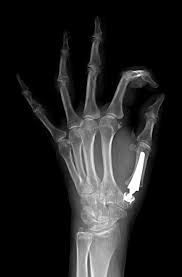

Cirugía:

Puede realizarse de varias maneras:

1) Por interposición de partes blandas.

2) Cirugía de fusión: se realiza artrodiesis con placa o tornillos para fijar la articulación.

3)Prótesis de la articulación: se reemplaza el cartílago y hueso dañado por una protesis de materiales inertes, conservando el funcionamieno del pulgar.